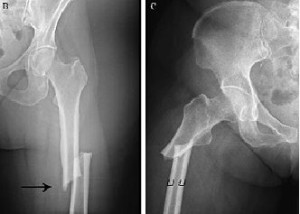

El uso prolongado de bifosfonatos reduce la resistencia a las fracturas

Luego de un uso promedio de 8 años, los bifosfonatos mostraban tejido cortical más mineralizado pero con menor resistencia al inicio y progresión de la fractura femoral. PNAS, 31 de julio de 2017